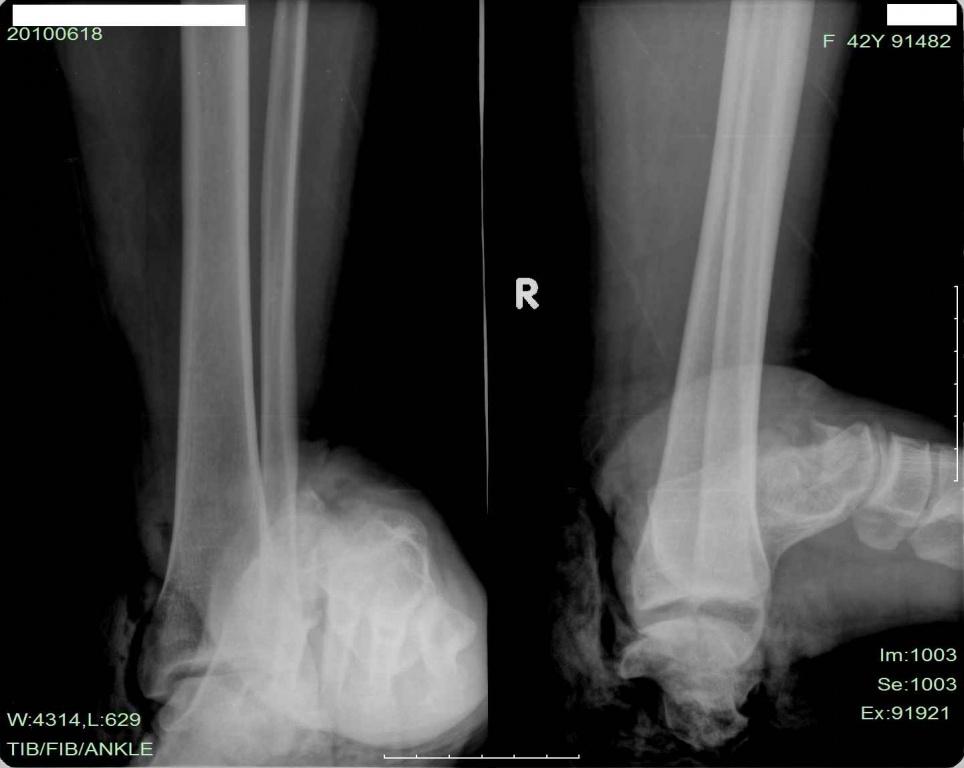

本帖最后由 wangshunzhi 于 2010-6-30 23:18 编辑 患者江某,女,42岁,外伤致左踝疼痛,畸形,流血8小时入院。

术中见:胫后神经呈马尾状撕断,胫后血管未断,搏动可。距骨颈骨折,距骨体内前方骨折,距下关节脱位,踝管破裂,踝管内肌腱脱位,腓骨肌上支持带破裂,腓骨长短肌腱脱位。